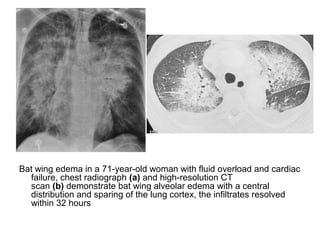

Bat wing edema in a 71-year-old woman with fluid overload and cardiac

failure, chest radiograph (a) and high-resolution CT

scan (b) demonstrate bat wing alveolar edema with a central

distribution and sparing of the lung cortex, the infiltrates resolved

within 32 hours